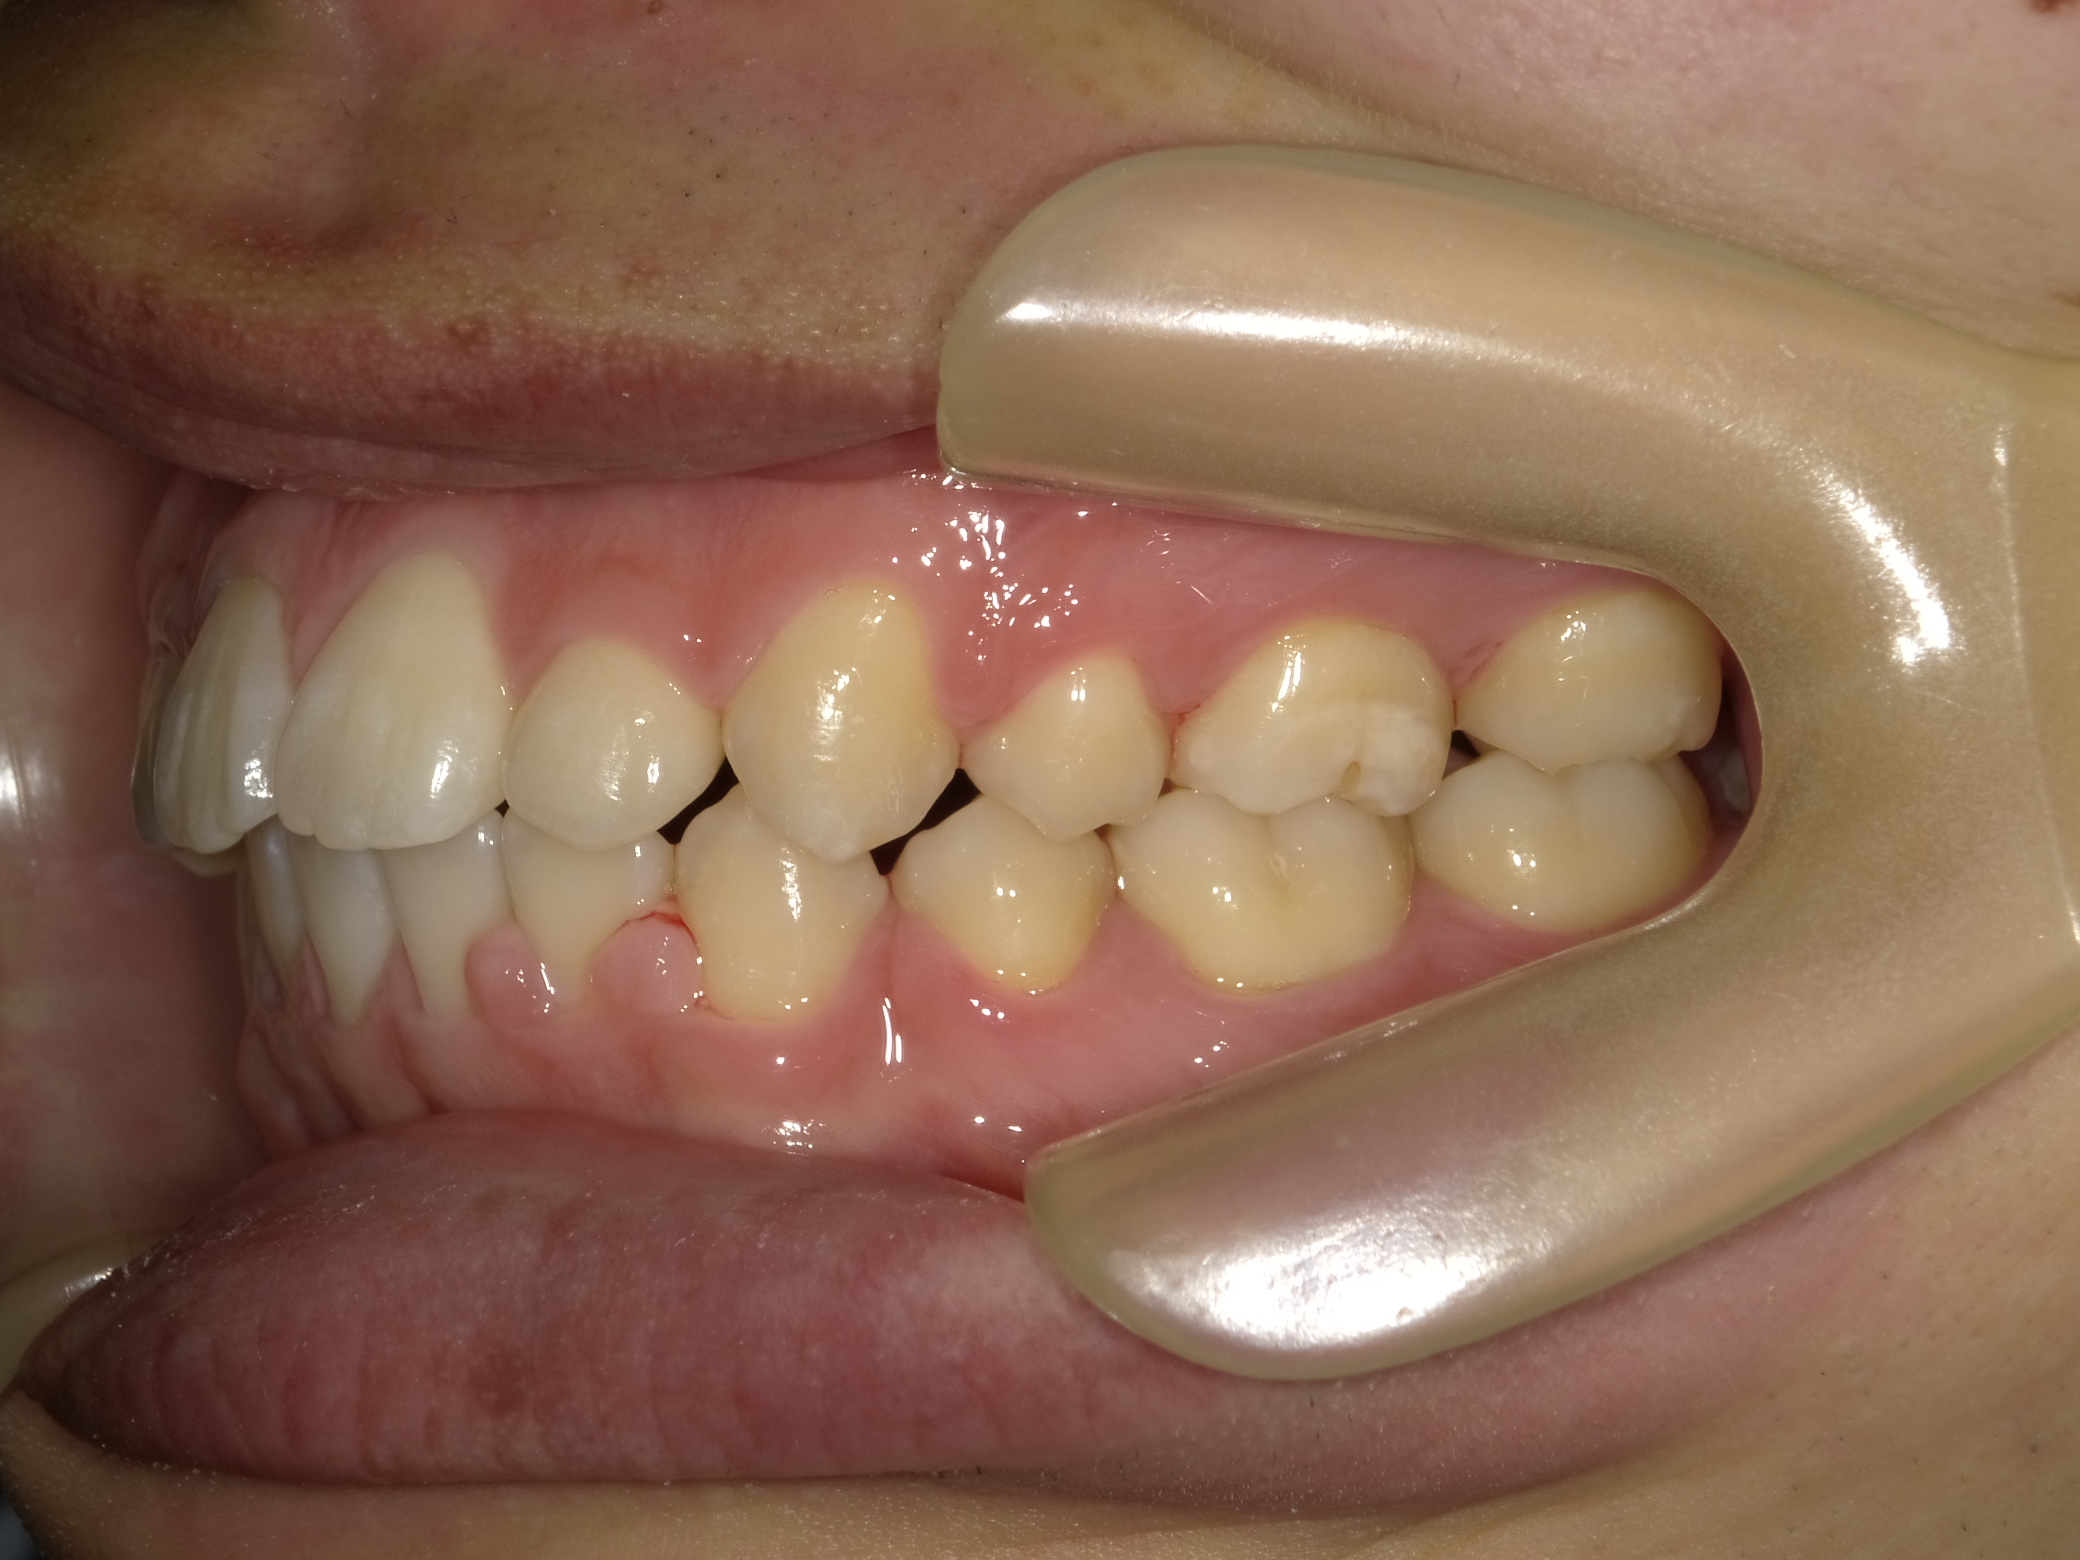

| 症例分類 | 上下顎前突 |

|---|---|

| 主訴 | 前歯が出ていて、口が閉じにくい |

| 年齢 | 20歳0ヶ月 |

| 性別 | 男性 |

| 抜歯部位 | 上下顎両側第一小臼歯 |

| 使用装置 | 歯の表側からのマルチブラケットによる矯正装置 |

| 治療期間 | 2年10ヶ月 |

| 保定装置 | 取り外し式保定装置 |

| 費用 | 相談料0円、検査料55,000円 動的矯正治療費935,000円 調整料6,600円×28回分 保定装置料0円 |

| リスク・注意点 | 上下の個々の歯の大きさに対して上下の顎が小さく歯が並ぶスペースが不足したために上下の前歯が前方に傾斜して、上下顎前突が生じています。これらを改善するために、上下顎両側第一小臼歯を抜歯して、このスペースを用いて歯を排列しました。歯の動き方には個人差があり、予想された治療期間が延長する可能性があります。 治療中は矯正歯科装置が歯の表面に付いており、歯が磨きにくくなるため、むし歯や歯周病が生じるリスクが高まります。ハミガキを適切に行ってお口の中を常に清潔に保ち、さらに、かかりつけ歯科医に定期的に受診することが大切です。 顎間ゴムの使用状況、定期的な通院など、矯正歯科治療には患者さんの協力が必要であり、それらが治療結果や治療期間に影響します。 治療の経過によっては当初予定していた治療計画を変更する可能性があります。 歯を動かすことにより歯根が吸収することがあります。 保定装置の装着時間が十分確保できない場合、歯並びや、咬み合せの「後戻り」が生じる可能性があります。 |